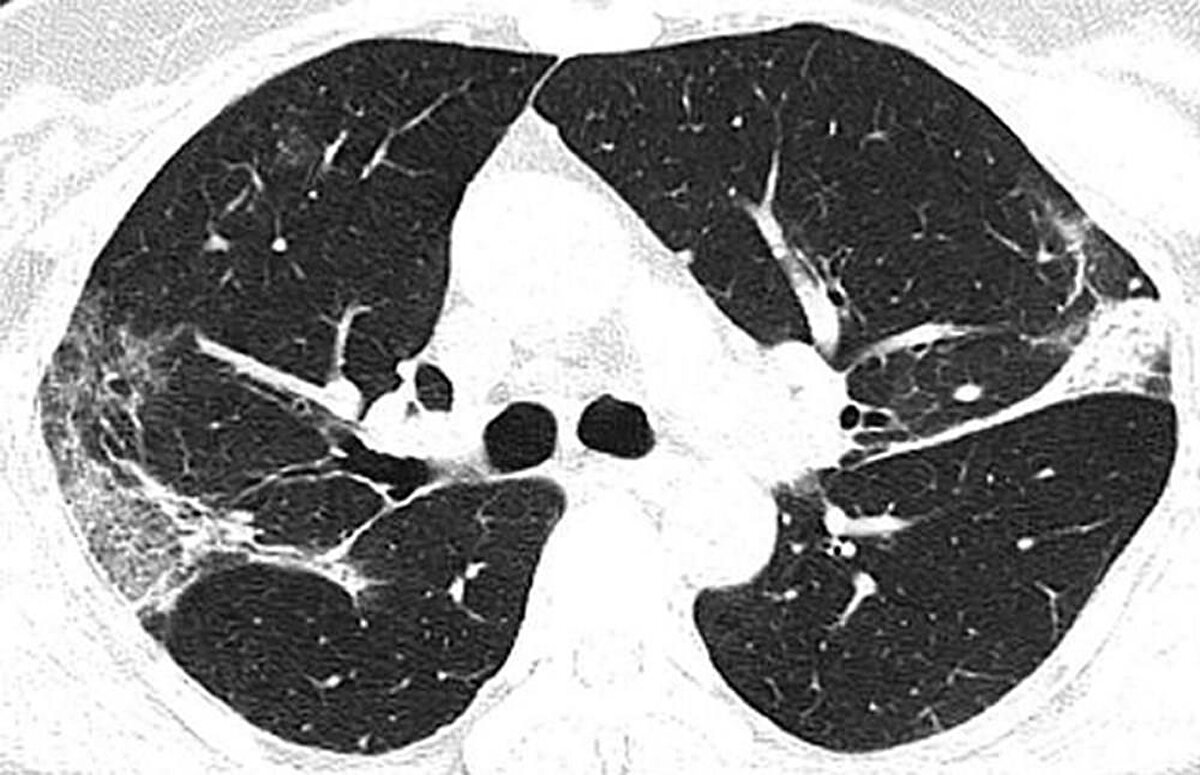

Çin'in Hubey eyaletine bağlı Wuhan'daki salgının kaynağı olduğu düşünülen hayvan pazarında çalışan 44 yaşındaki bir Çinlinin röntgen filmleri yeni tip corona virüsün akciğerlere verdiği zararı açıkça gösteriyor. Filmlerde akciğerdeki hava boşluklarının çoğunluğunun virüs nedeniyle dolduğu görülüyor. Uzmanlar, taramalarda görülen beyaz lekelerin SARS ve MERS'te de mevcut olduğunu belirtti.

Kuzey Amerika Radyoloji Derneği (RSNA), yeni tip corona virüsün (Covid-19) ortaya çıktığı Çin’in Wuhan kentindeki salgının kaynağı olduğu düşünülen deniz ürünleri pazarında çalışan ve 44 yaşında virüs nedeniyle hayatını kaybeden bir adamın röntgen filmlerini kamuoyuyla paylaştı. Filmlerde corona virüsün akciğerleri nasıl tahrip ettiği net bir şekilde görülüyor.

Hava kesecikleri doluyor X-ray ışını taramalarında corona virüsün etkileği yerler beyaz olarak görülüyor. Uzmanlar, hastada virüsün akciğerlerdeki hava keseciklerini kısmen doldurduğunu ve akciğer nodüllerine sebep olduğunu belirtti. .Diğer taraftan aynı tip anormalliklerin SARS (Şiddetli Akut Solunum Sendromu) ve MERS (Ortadoğu Solunum Sendromu) vakalarında da görüldüğünü söylediler.